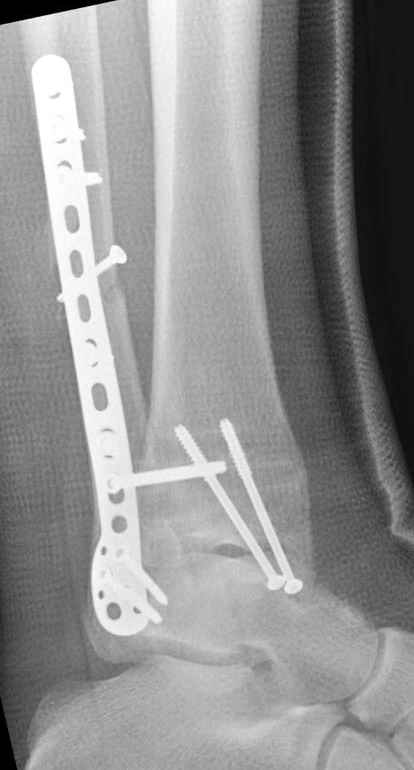

Ниже рентгенограммы

12 января прямой

|

12 января боковой

12 января трехчетвертной

Риторический вопрос - в каком руководстве рекомендован такой способ остеосинтеза наружной лодыжки?

Очевидно, такой результат операции был запрограммирован. При невосстановленной длине и практически нефиксированной малоберцовой кости (этот кортикальный винт - как карандаш в стакане), при неустраненном подвывихе, невправленной и тоже нефиксированной внутренней лодыжке нет стабильной вилки сустава. Если такую операцию сделать даже сразу, а не через 4 месяца, то результат ожидаем

Вариант с артродезом уже обсудили. Хотя, после увиденых снимков, пессимизм насчет восстановительной операции у меня, например, несколько уменьшился. Особенного уж какого-то остеопороза не видно даже на январских снимках. Можно черед мини-доступы убрать винты, аппаратом вправить малоберцовую кость, устранить подвывих стопы. Ну а дальше фиксировать малоберцовую пластиной сзади. А может, и напряженной Y-спицей попробовать - Анатолий Федорович, как Вы полагаете? Внутреннюю - то, что осталось, если уже не получится сделать спицами и проволокой, то что-то типа пластики дельтовидной связки. А может, и не трогать ее вовсе... В общем, выбор непростой,

много факторов надо взвесить.

Если до сих ничего не сделано, с артродезом сустава в данный момент я бы повременил, на выставленных январских снимках хорошо сохранившийся сустав, а в "мортиз" (трехчетвертной) и на боковых снимках не менее 5 мм укорочение малоберцовой кости. Косые переломы лучше фиксировать пластинами, как то мы разбирали случай, где было отмечено, что это закон "таранная кость всегда следует за малоберцовой".

тарнная кость находится в латеральном подвывихе, что снижает шансы этого сустава.

Это видно по снимку - середина суставной поверхности тарана должна быть против середины суставной поверхности тибии. Причины, что это не так:

1. Внутренняя лодыжка не на месте

2. наружная лодыжка укорочена

3. Возможно есть компрессионный перелом наружной части пилона тибии.

В подобных случаях лучше всего начинать с главной цели - вправить таран, временно зафиксировать спицами и используя таран как шаблон поставить на место лодыжки, неважно в какой последовательности.